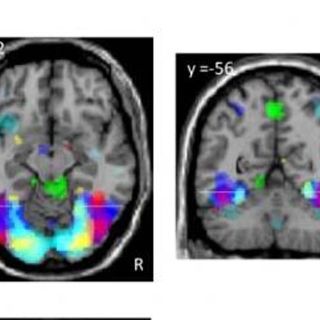

PARIS, FRANCIA (14/NOV/2010).-La alfabetización, la capacidad de leer y escribir, es algo muy reciente en la historia del ser humano, por lo que el cerebro debió recurrir a lo que ya tenía para hacer frente a esta nueva e importante actividad mental y no habría desarrollado mecanismos nuevos, genéticos o de desarrollo, algo que exige bastante tiempo evolutivo, creen los científicos. Unos investigadores han hecho ahora unos experimentos curiosos para medir su huella en el cerebro, analizando con técnicas de resonancia funcional el cerebro de 63 voluntarios brasileños y portugueses: 11 analfabetos, 22 alfabetizados ya de adultos y 31 que aprendieron a leer y escribir de niños.

Han identificado así las regiones cerebrales moduladas en la alfabetización, que están en zonas ya conocidas por su especialización en el vocabulario y en el reconocimiento visual de caras. Además la alfabetización mejora las funciones del habla. Todavía no saben si estos cambios en la anatomía cerebral, esta especialización dedicada a leer y escribir, merman o no la capacidad, por ejemplo, de reconocer rostros.

La alfabetización, ya sea adquirida en la infancia o en la edad adulta, refuerza la respuesta cerebral de varias maneras, explican Dehaene y sus colegas. Por un lado relanza la organización de la corteza visual, pero también permite que, en respuesta a frases escritas, se active toda la red del lenguaje hablado en el hemisferio izquierdo. "La capacidad de leer, una invención cultural tardía, se aproxima a la eficiencia de la vía de comunicación más evolucionada de la especie humana, que es el habla", explican en Science.